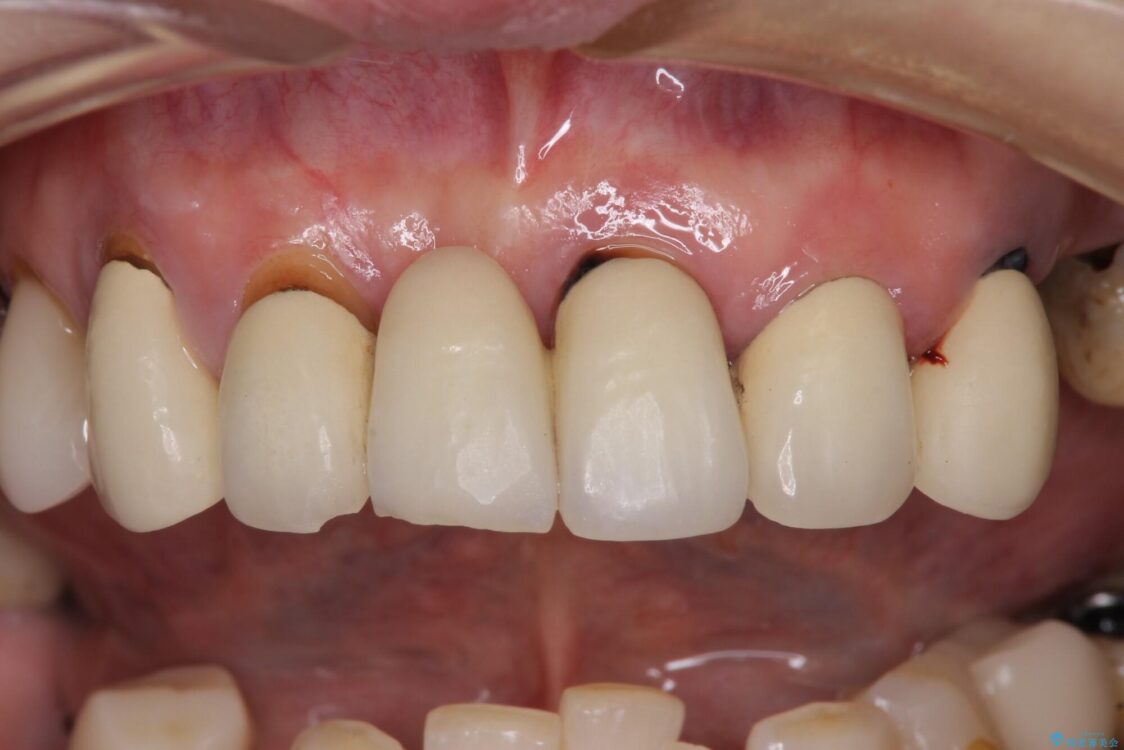

治療前

• 放置したインプラントとインビザライン 全顎リカバリー治療 治療前画像

治療途中